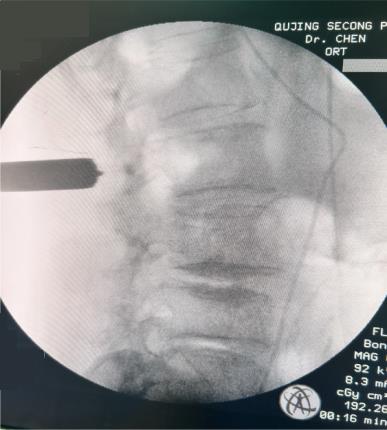

摘要:目的 观察单通道非同轴脊柱内镜经椎间孔外入路(椎板外切迹)治疗极外侧椎间盘突出症(FLLDH)的临床疗效。方法 回顾性分析2022年5月-2024年5月该院收治的,行单通道非同轴脊柱内镜经椎间孔外入路(椎板外切迹)治疗的FLLDH患者70例。于术前和术后,评估腰腿疼痛程度、腰椎功能和临床疗效。结果 相较于术前,术后3 d和3个月,患者下肢视觉模拟评分法(VAS)评分、腰部VAS评分、Oswestry功能障碍指数(ODI)、数字分级评分法(NRS)评分和Roland-Morris功能障碍问卷(RMDQ)评分明显降低,日本骨科协会(JOA)评分明显升高,差异均有统计学意义(P < 0.05);改良MacNab评分标准显示,末次随访时的优良率为94.28%。结论 单通道非同轴脊柱内镜经椎间孔外入路(椎板外切迹)治疗FLLDH,能明显改善患者腰腿疼痛和腰椎下肢功能,其具有创伤小、易操作、安全性高和疗效好等优点,值得在临床推广应用。